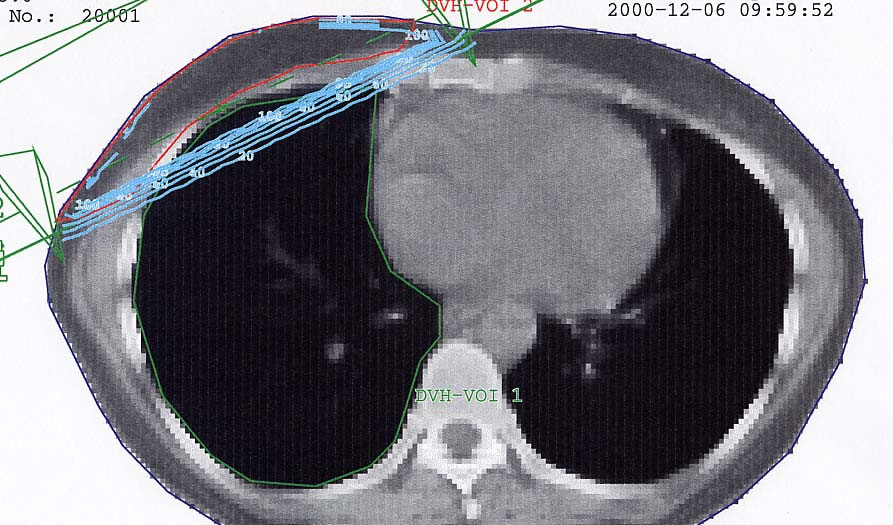

Mammakarzinom: Bestrahlungsplan

Bestrahlungspläne